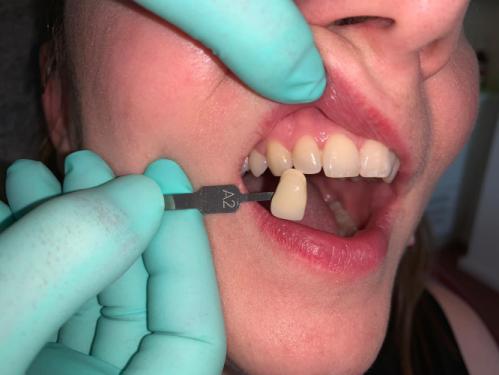

Die Vorteile liegen auf der Hand: Wir können schnell und in direkter Zusammenarbeit mit unseren Technikerinnen hochwertige Arbeiten anfertigen. Gerade bei der individuellen Farbgestaltung des Zahnersatzes profitieren Sie als Patient von der engen Zusammenarbeit.

- Individuell geschichtete Keramikinlays / Veneers